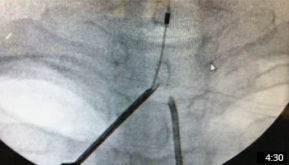

Dr. Brian Allen shows us his technique of using cryoanalgesia to treat pain of the plantar fascia on a cadaveric foot. He explains the initial incision, probe placement, and freezing times. Dr. Allen also explains why cyroanalgesia is a less invasive and much safer than surgery.